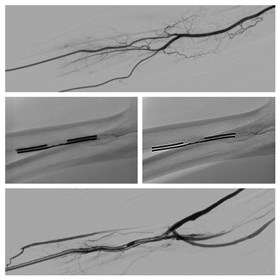

Dialisi, accesso vascolare senza bisturi

Nuova tecnica applicata al Cannizzaro per la prima volta in Italia